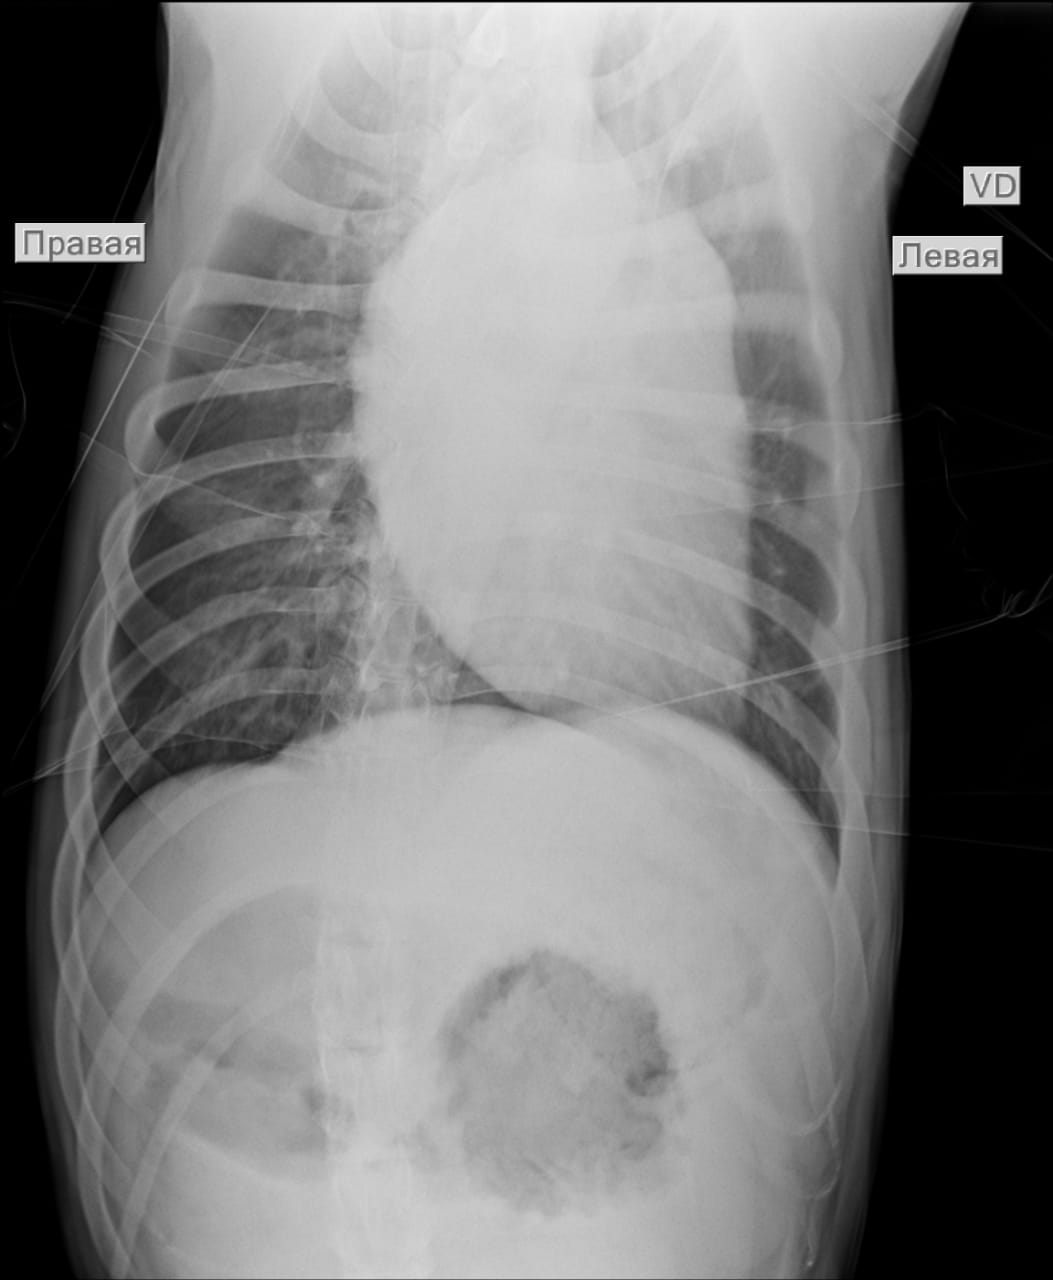

Анализы Арчи. Сердца и легких

Вложения

IMG-20220719-WA0100.jpg

IMG-20220719-WA0102.jpg

IMG-20220719-WA0104.jpg

IMG-20220719-WA0103.jpg

IMG-20220719-WA0105.jpg

Сегодня Арчуна Ирина возила на рентген легких и сдали анализ мочи. Результат анализа мочи готов будет завтра. Рентген легких выставляю.

Ирина, ждем твоего вердикта по рентгена и можно ли нам готовить Арчи к операции по глазам.

Антибиотика курс пропили.

Лучше чем было, но явно не норма:(